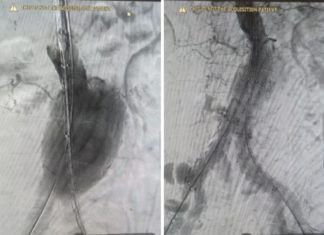

«Корсет» для аневризмы: в Волгограде провели сложную операцию без открытого вмешательства

В Областной больнице № 1 врачи успешно провели сложную операцию по установке стент-графта. Эта процедура была необходима для лечения аневризмы брюшной аорты. Разрыв аорты был опасен для жизни. Чтобы его предотвратить, а аневризма была достаточно...